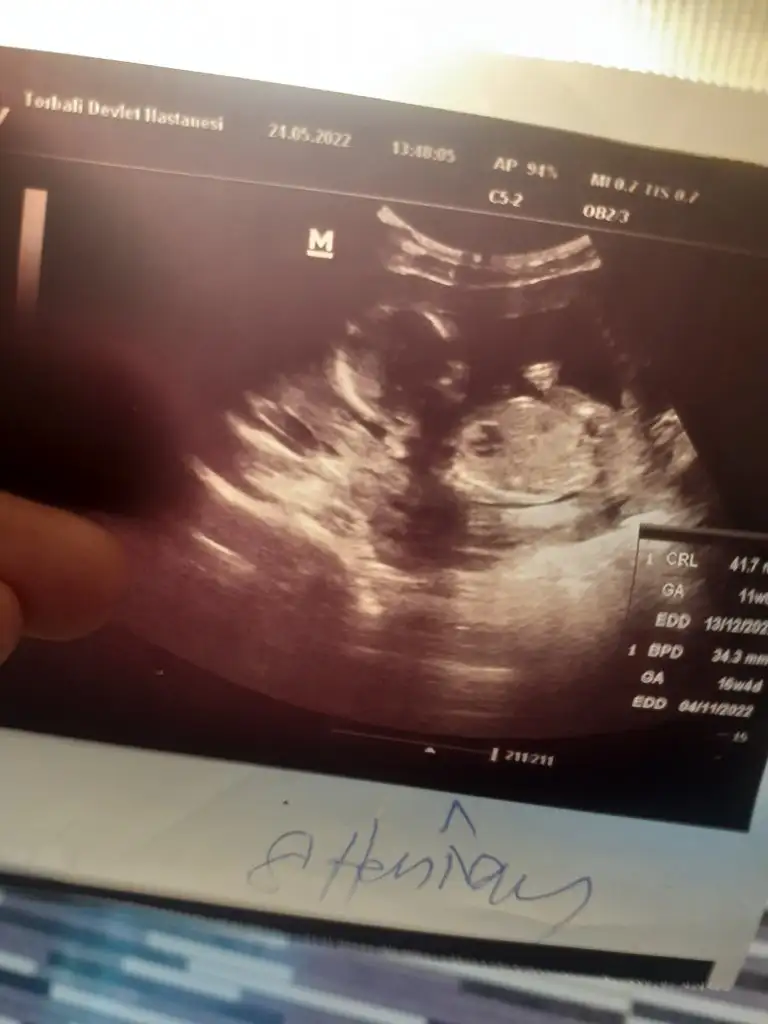

9+3 karından bakabilir misiniz?

• 7067D3E8-1C1A-474D-A2D6-75770CD3E592.webp

7067D3E8-1C1A-474D-A2D6-75770CD3E592.webp

14,8 KB · Görüntüleme: 60